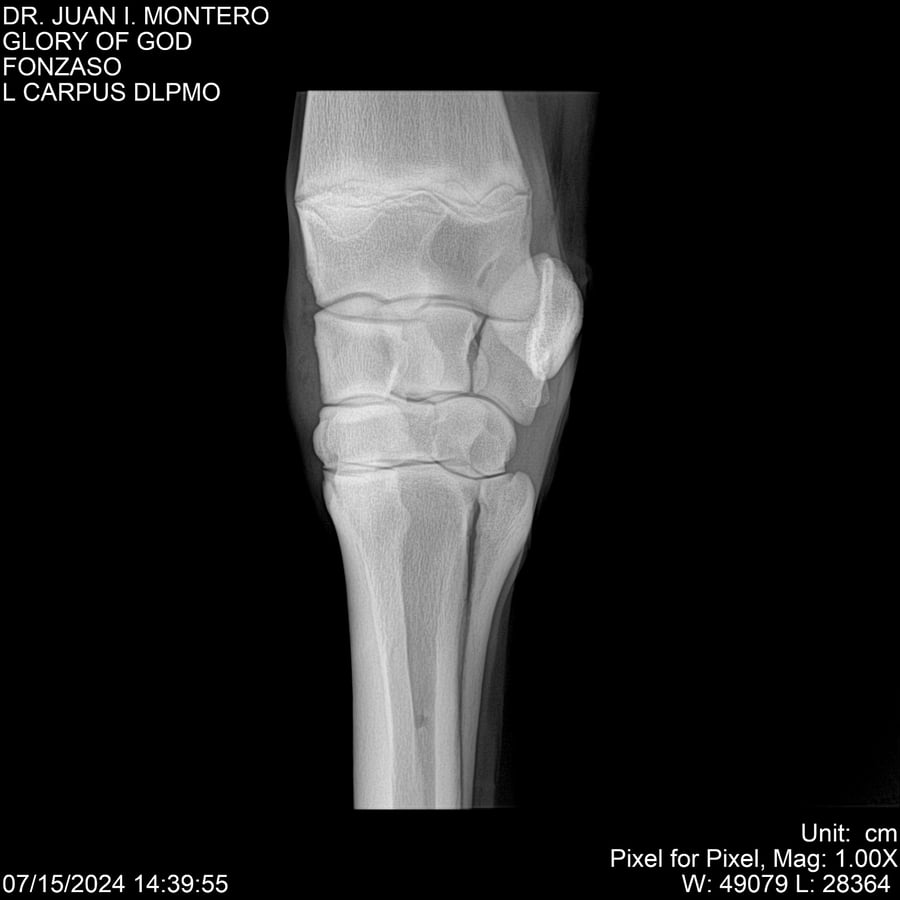

LOTE 10, GLORY OF GOD 🔥 🔥 🔥 Lote Anterior Volver al remate Lote Siguiente Ficha Contacto Montevideo - Ficha del Lote Identificador: #281389 Categoría: Yeguarizos Montevideo - 115 Visualizaciones ClicData Contacto Empresa: Abelenda N. R., Walter Hugo Nombre*: Teléfono* : E-mail* : Mensaje Enviar Registrese gratis Este contenido Exclusivo está disponible sólo para usuarios registrados Ingresar